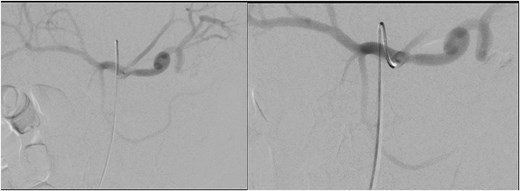

He was treated with tranexamic acid and blood transfusion due to bleeding as evident on computed tomography (CT) angiogram that was exacerbated in the setting of anticoagulation. He then underwent angioembolization with interventional radiology. The angiographic finding of a pseudoaneurysm arising from a pancreatic branch off the SMA was embolized (Fig. 9).

Angioembolization of pseudoaneurysm arising from pancreatic branch off SMA.

Limited case reports of PPP have mentioned the presence of pancreatitis complications. This is first case report describing PPP syndrome with a bleeding pseudoaneurysm into the peripancreatic collection. Pancreatic pseudoaneurysm is an uncommon vascular complication of pancreatitis, resulting from erosion of a peripancreatic artery into a pseudocyst [8]. The splenic artery is the most frequently affected, with the gastroduodenal, pancreaticoduodenal, and hepatic arteries following in order of occurrence [9]. It commonly presents as gastrointestinal bleeding secondary to rupture or abdominal pain, and a bleeding pseudoaneurysm is potentially lethal. Diagnosis is usually made with CT arterial phase. Once the diagnosis is made the patient will then proceed to angiography in attempt for angioembolization. Endovascular therapeutic options such as angioembolization provides notable benefits such as reduced postoperative pain, shorter hospitalization, and quicker resumption of daily activities [10]. If embolization fails or if rebleeding occurs after embolization, options include direct ligation of the bleeding vessel or surgical resection of the pancreas along with the pseudoaneurysm [11].